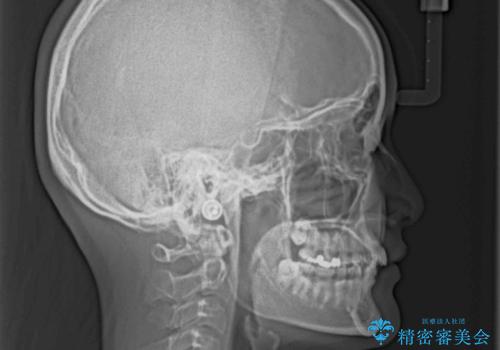

奥歯の咬み合わせは上顎に対して下顎が後方位にあり、上顎前歯で下顎前歯が隠れるような典型的な過蓋咬合です。

補助装置を用いて上顎大臼歯を後方に移動させながら、ワイヤー装置で歯列を整えて深い咬み合わせを挙上することとしました。